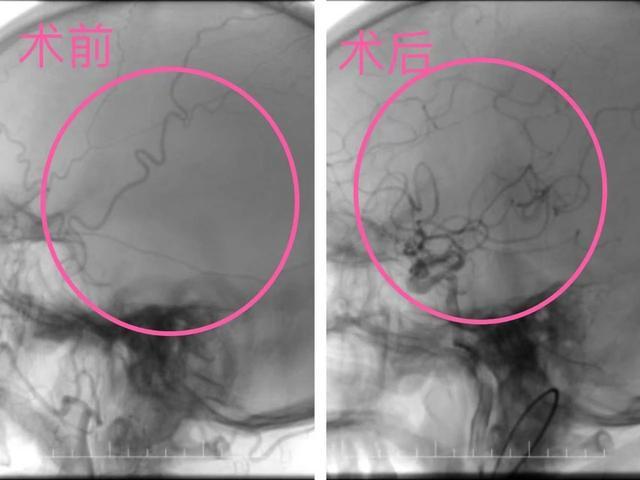

次日清晨,杨爷爷左侧肢体再次瘫痪,情况危急!神经内科团队迅速响应,考虑颅内大血管再闭塞,立即在DSA引导下行急诊动脉取栓术,成功开通闭塞的颈内动脉,血流恢复通畅。

▲从突发瘫痪到血流再通

术后第二天,杨爷爷左侧肢体可抬离床面并抵抗部分阻力。从突发瘫痪到血流再通,每一分钟的争取,都能降低患者的脑细胞损伤,影响预后!